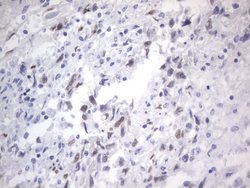

RBFOX1 Mouse anti-Human, Clone: OTI4F9, lyophilized, TrueMAB™

| Immunohistochemistry (Paraffin), Western Blot | |